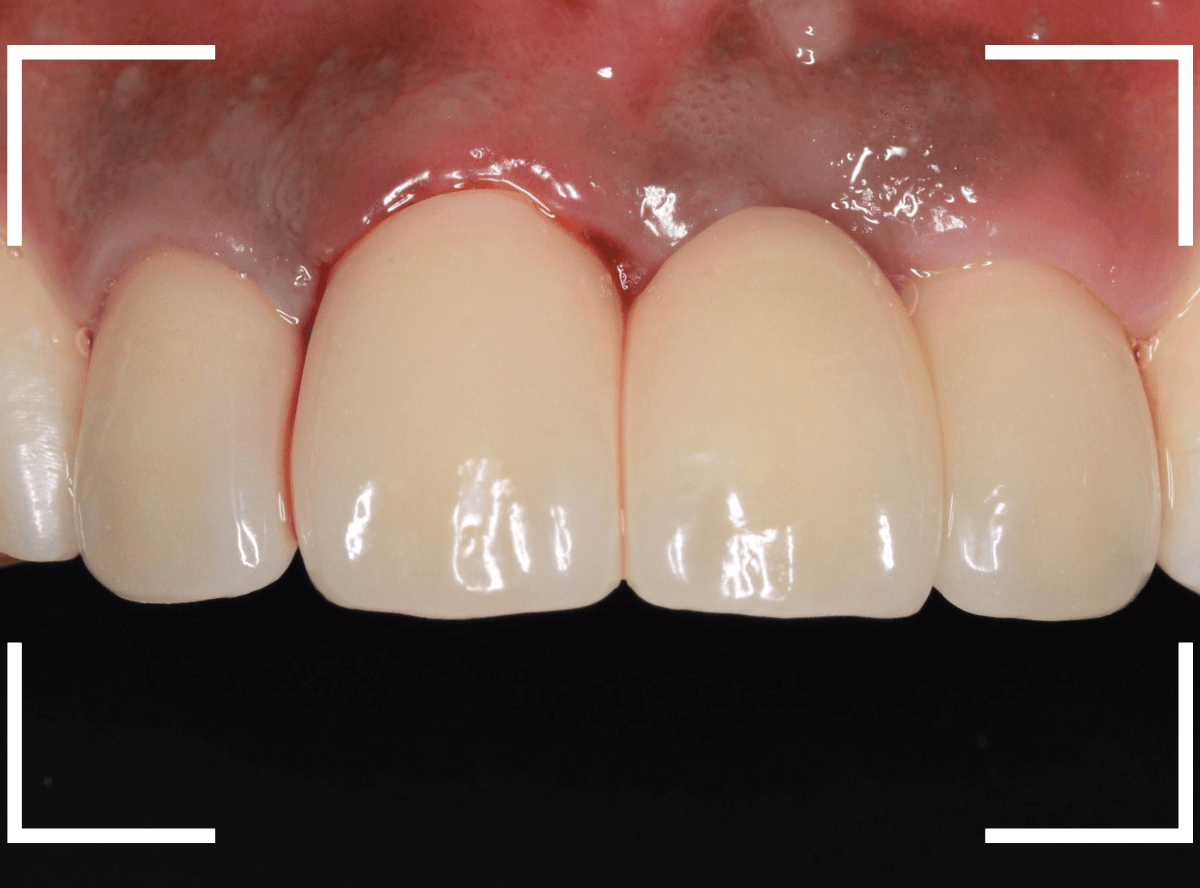

しばらく経過観察して、歯肉が落ち着いたところです。

さし歯を入れるのに心配ない程度の歯の高さが確保でき、さし歯を作るための準備が整いました。

今回は、審美性と、清掃性が高く、歯周病が進行しにくいという利点を考慮して、ジルコニア・セラミックでの治療を選択されました。

ジルコニア・セラミックset後の状態です。

仮歯で細かく調整したおかげで、下の歯のかみ合わせは若干の調整で済む事ができました。

set前との比較です。